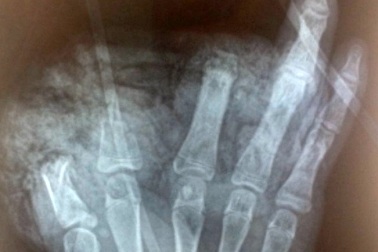

Thiếu niên 14 tuổi bị cụt 3 ngón tay vì nghịch pin quạt tích điệnCậu thiếu niên ở Bắc Ninh đang nghịch pin của quạt tích điện thì thì quả pin bất ngờ phát nổ khiến em bị thương nghiêm trọng.